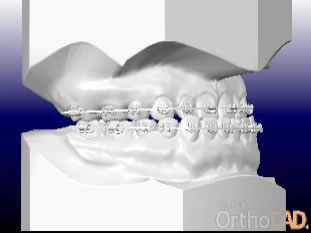

さまざまな問題をふくんでいたので、最新のCAD技術を応用した矯正治療分析ソフトを用いて治療計画を立てて、動画で治療経過予測を説明しています。

こちらに示しているのは治療開始時、手術直前予測、手術後予測の3段階静止画像ですが、実際のCADでは治療経過を動画で表現しています。

右横から見た

治療前、手術前、手術後の予測CAD

(表示を歯だけにして、前歯の変化をわかりやすくしました)